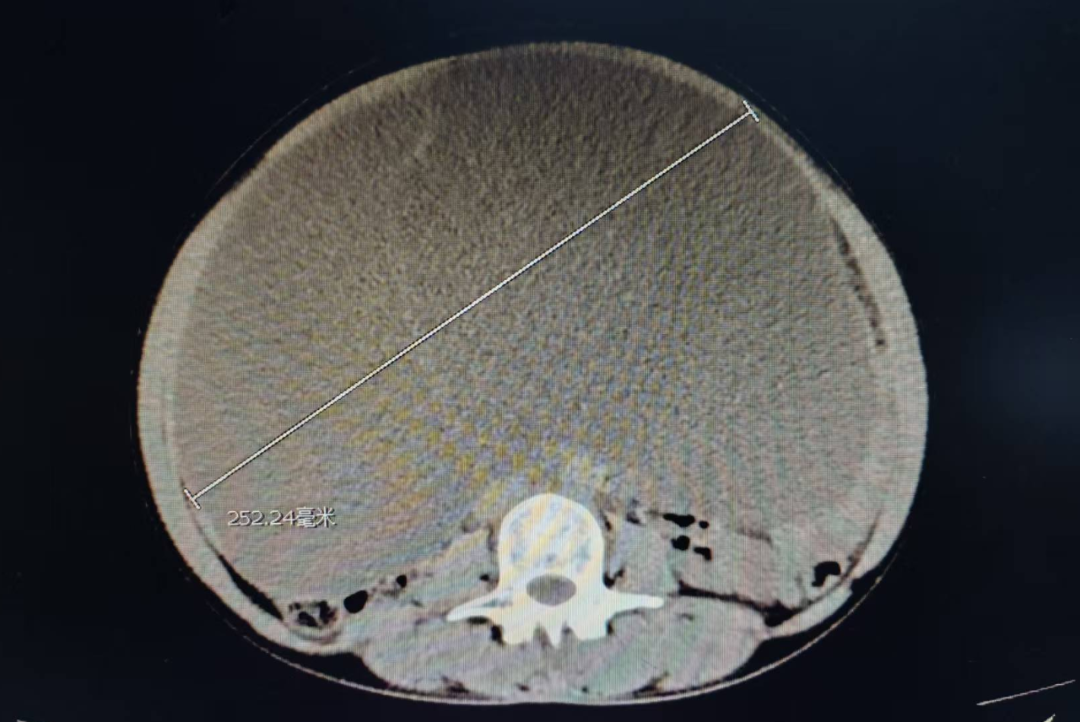

接诊的妇科主任钟雪辉一眼就注意到了异常——患者卢阿姨的肚子鼓得像足月孕妇一样,按压时还伴随着明显压痛。但卢阿姨已绝经多年,反常的“孕肚”让钟雪辉立刻警觉起来。凭借多年临床经验,钟雪辉判断卢阿姨腹腔内大概率存在异常包块,当即安排检查。结果显示:卢阿姨卵巢上长了一个25.2厘米的巨大包块。

面对这一巨大包块,可选择传统开腹手术或微创手术。传统开腹手术切口大、创伤重,术后恢复慢,对于老年患者来说,不仅痛苦大,还可能增加并发症风险;而微创手术切除这种巨大包块,对医生的要求很高。卢阿姨强烈要求做微创手术,希望能少遭罪、恢复快。

钟雪辉团队与患者及家属反复沟通后,最终为卢阿姨实施了单孔腹腔镜下双侧附件(卵巢、输卵管)切除术。手术中抽出的囊内液高达11000毫升,相当于22瓶500毫升的矿泉水。